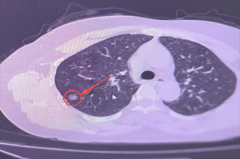

【精准“导航”+无痛定位】南通六院胸外科黑科技让“刁钻”肺结节无处可藏!

肺结节位置太深、藏在骨头缝里? 传统定位又疼又有辐射? 别担心!南通六院胸外科黑科技 CT三维数据融合式经皮穿刺导航定位术 2分钟精准锁定病灶,...